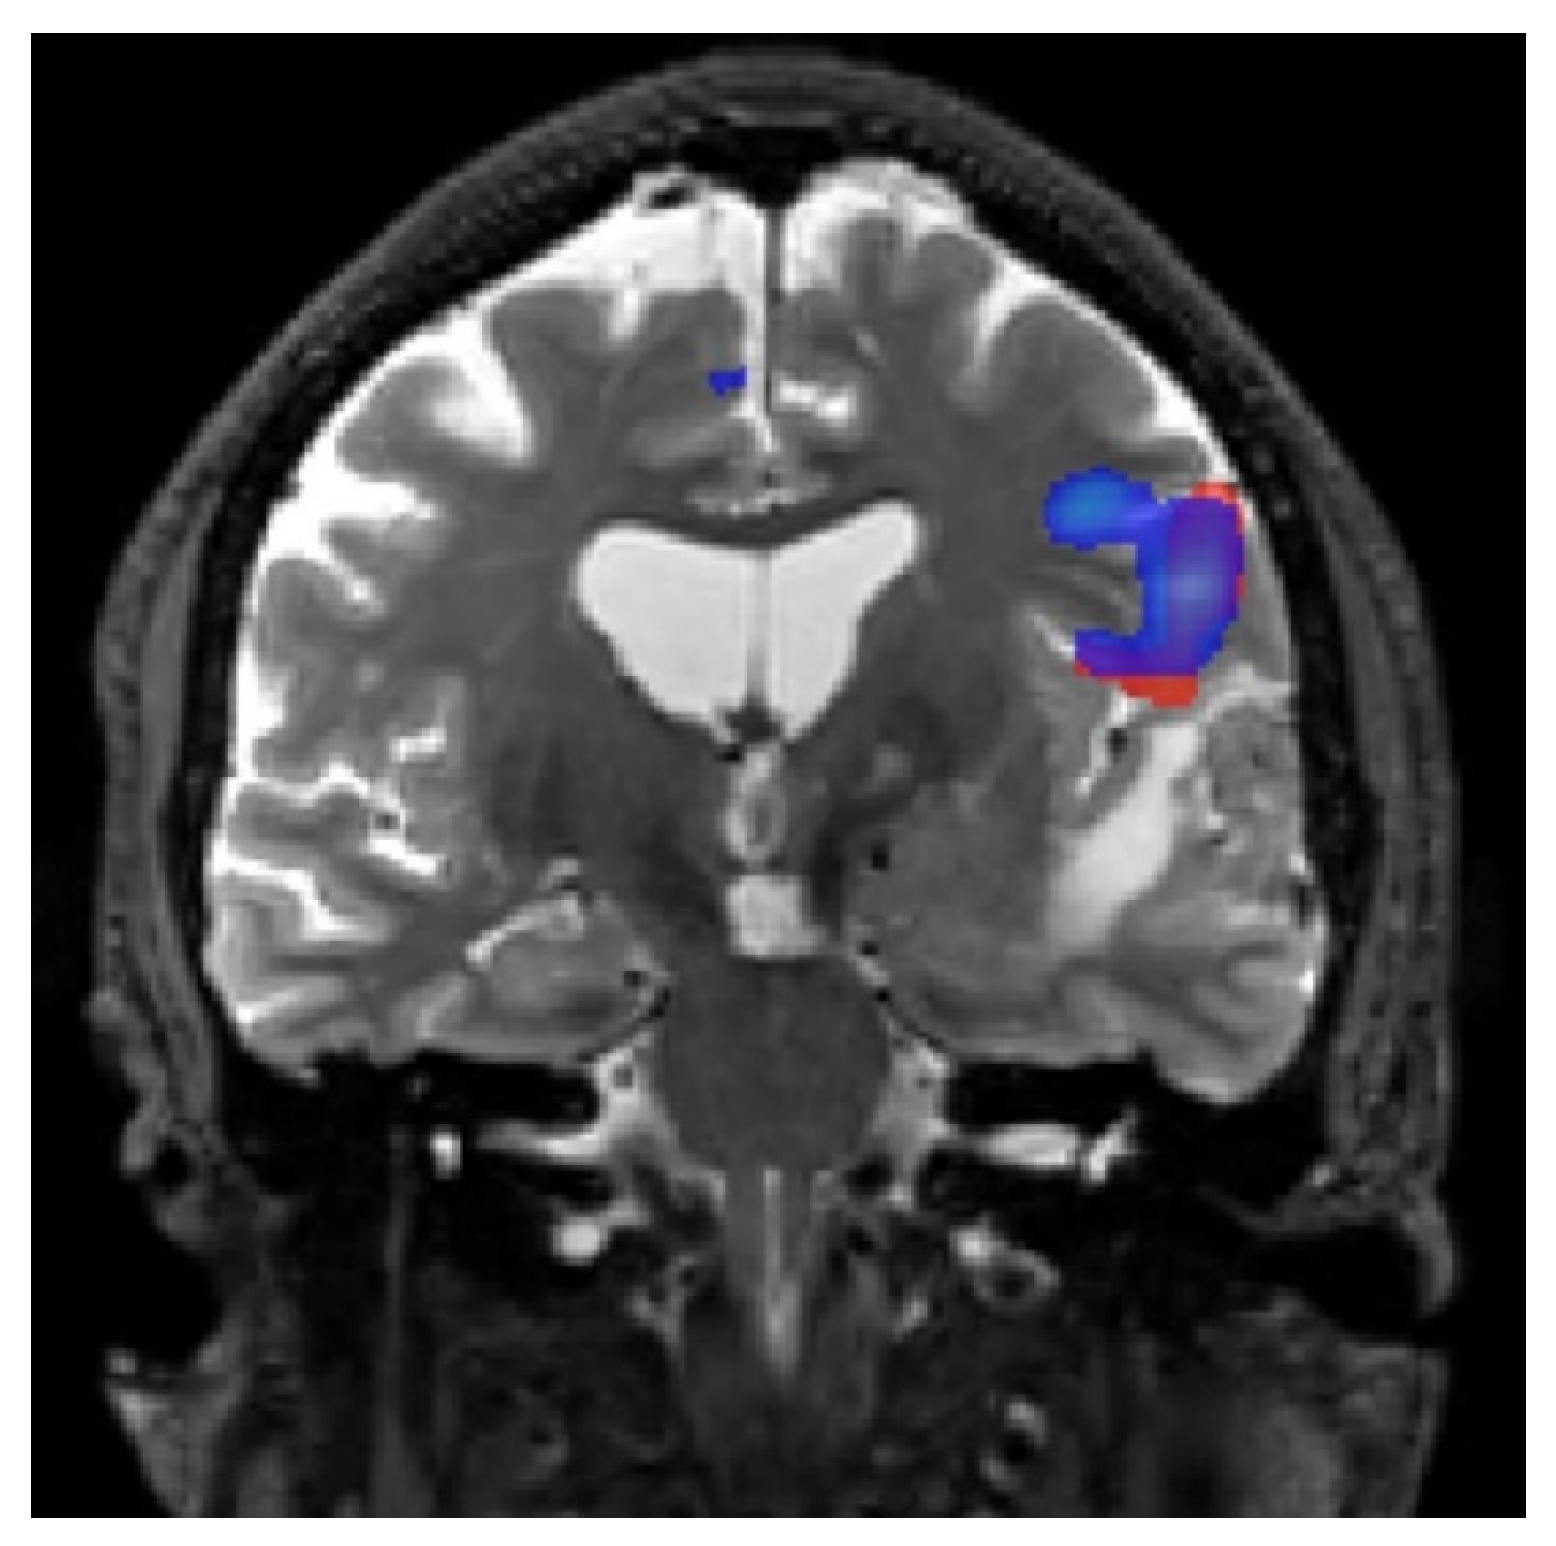

5.1. fMRI of Motor and Somatosensory Functions

- When the anatomy is effaced or partially effaced, and morphological Rolandic landmarks cannot be identified due to tumor growth;

- When a tumor lies in proximity to the identifiable motor hand area.